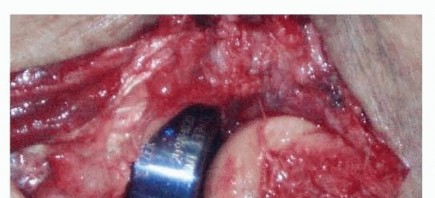

The lateral approach is the workhorse for the treatment of terrible triad injuries, providing access to the LCL complex, the radial head, and, in many cases, the coronoid. A direct lateral incision is made, typically utilizing the Kocher interval between the anconeus and the extensor carpi ulnaris (ECU). However, the astute surgeon will often abandon formal anatomic intervals and instead utilize the traumatic dissection that occurred at the time of injury. In most cases, the LCL and common extensor origin have been avulsed from the lateral epicondyle, creating a massive traumatic window directly into the joint. If an anteromedial facet fracture is present, a separate medial incision is utilized. The medial approach involves identifying and protecting the ulnar nerve, followed by splitting the flexor carpi ulnaris (FCU) or utilizing an "over-the-top" approach anterior to the medial epicondyle to gain orthogonal access to the coronoid.

Step 3: Repair the LCL Complex. With the osseous stabilizers reconstructed, the lateral ligamentous tension must be restored. The avulsed LUCL and common extensor origin are repaired back to their anatomic footprint on the lateral epicondyle—the isometric point located at the center of capitellar curvature. This is typically achieved using robust suture anchors or transosseous bone tunnels. The repair must be tied with the forearm in pronation and the elbow at 90 degrees of flexion to ensure appropriate tensioning of the lateral structures.